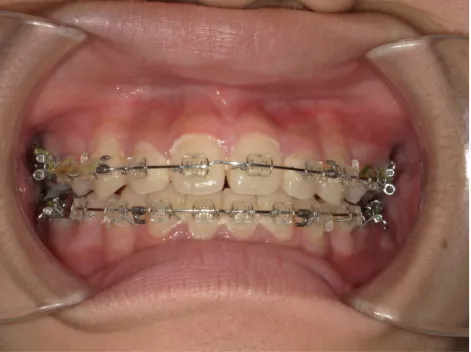

治療後⑩高2:17y7m 抜歯治療終了

口元の治療前後:15y5m→17y7m スッキリしました